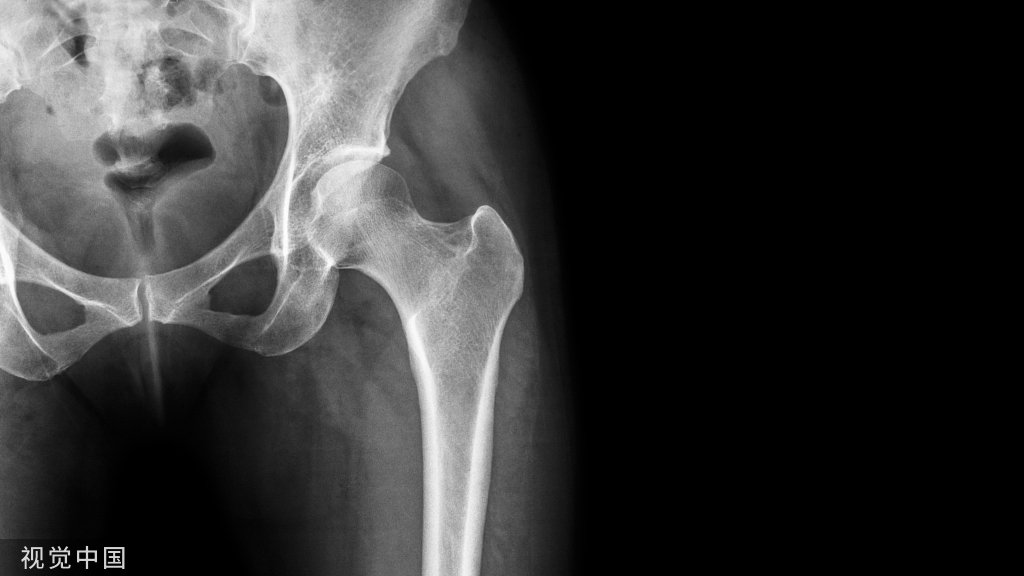

低能量损伤骨质疏松患者,在摔倒等低能量损伤时,也可能发生Hoffa骨折。